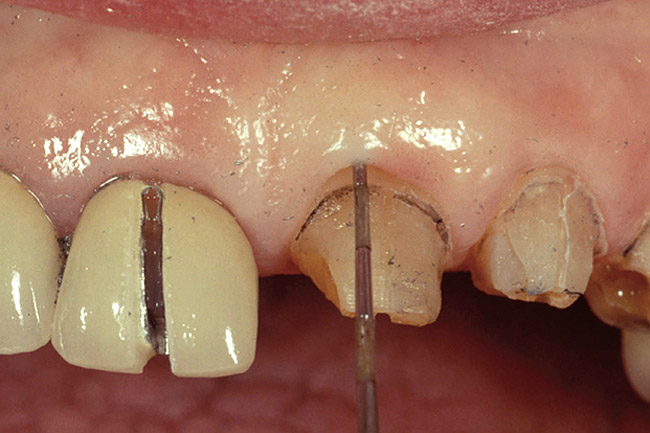

Figure 3  Dark teeth or teeth requiring restorations that are more opaque for masking often require the margin to be carried subgingivally, as with this central and lateral incisor.

Figure 3

Figure 4  View of the completed central and lateral incisor with margins placed subgingivally, but maintaining tissue health.

Figure 4